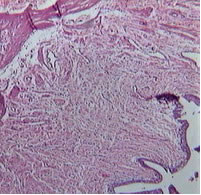

Второй тип: соединительной ткани по периметру мочеточника,

он занимает от 26 до 75% величины периметра.